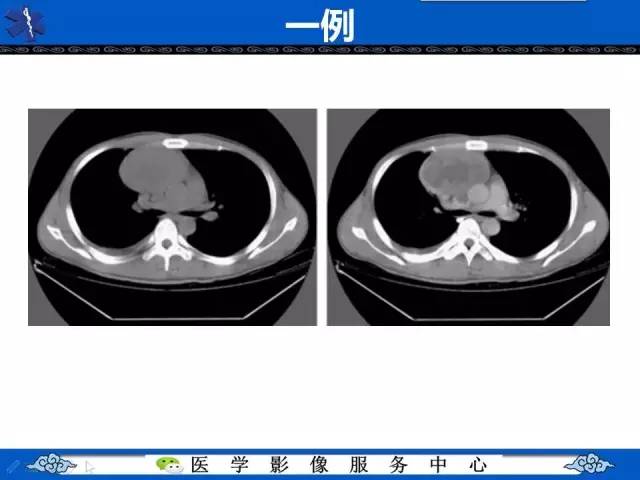

【病例】纵隔内胚窦瘤1例CT影像表现